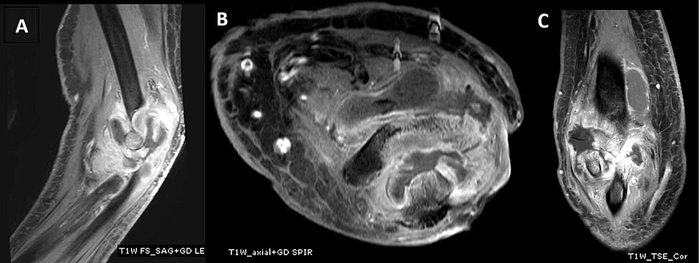

- МРТ - более точный метод диагностики, позволяет оценить состояние мягких тканей и костной ткани, увидеть отек кости, заподозрить остеомиелит.

Инфекционный артрит с остеомиелитом.